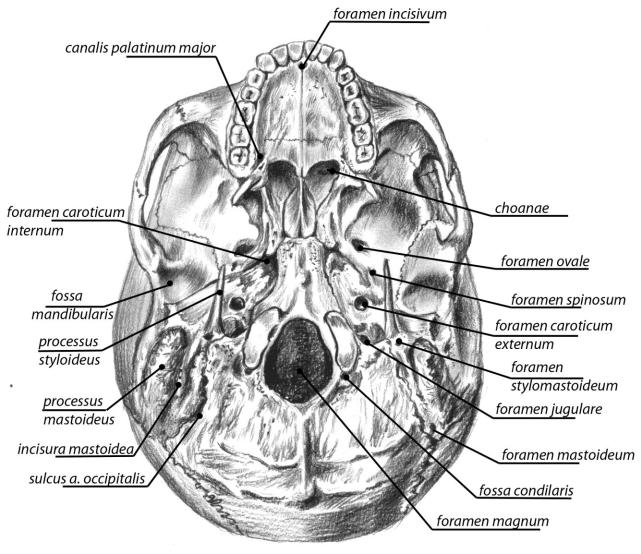

Анатомия и особенности фиссуры петротимпаника